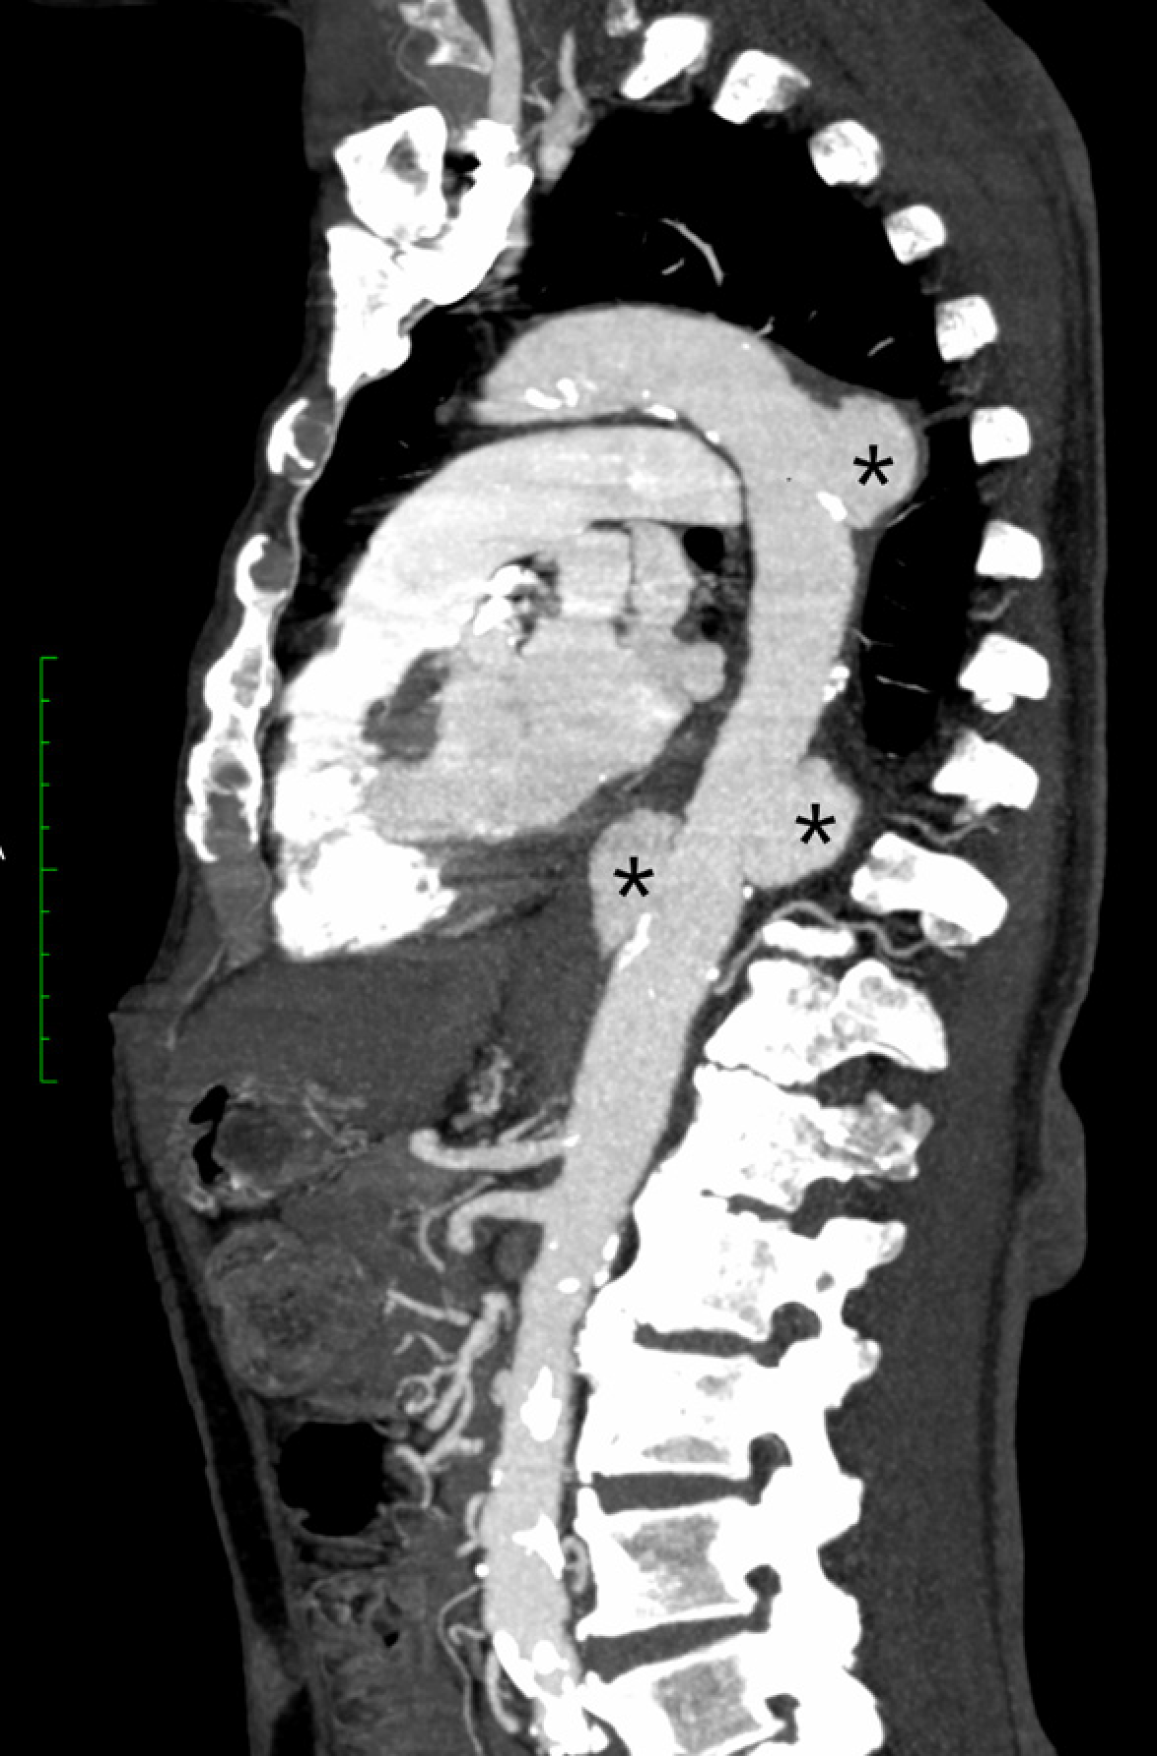

Figure 1 Sagittal view of computed tomography angiography of the thoracic aorta in maximum intensity projection showing three saccular aneurysms (*) along the descending thoracic aorta.

Background atherosclerotic changes of the visualized aorta are also noted.